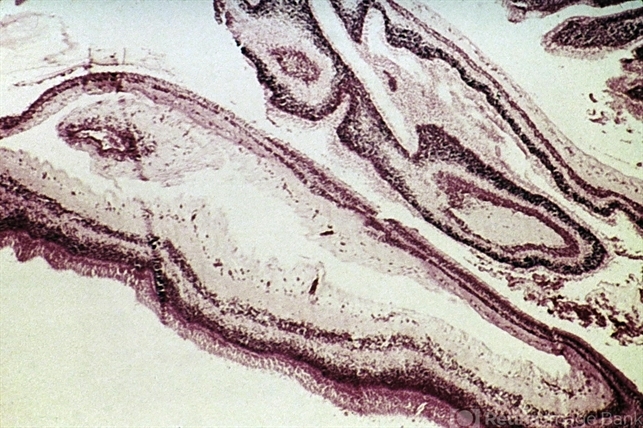

- scleral laceration

- Strips of retina removed from a scleral laceration.